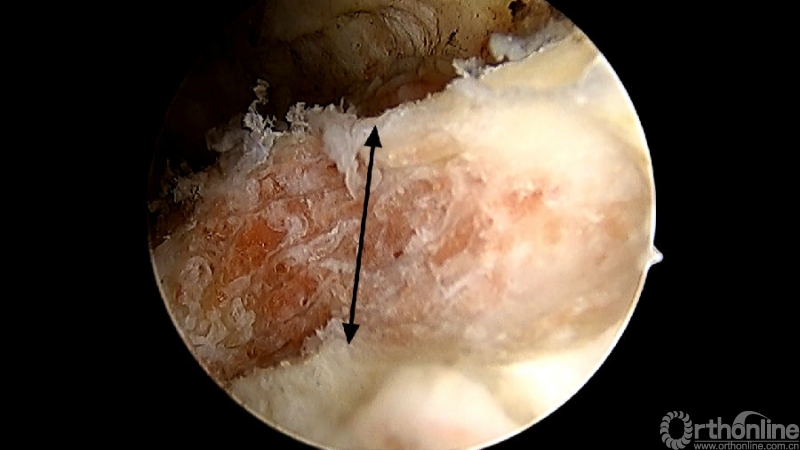

术中切除下关节突内缘的范围